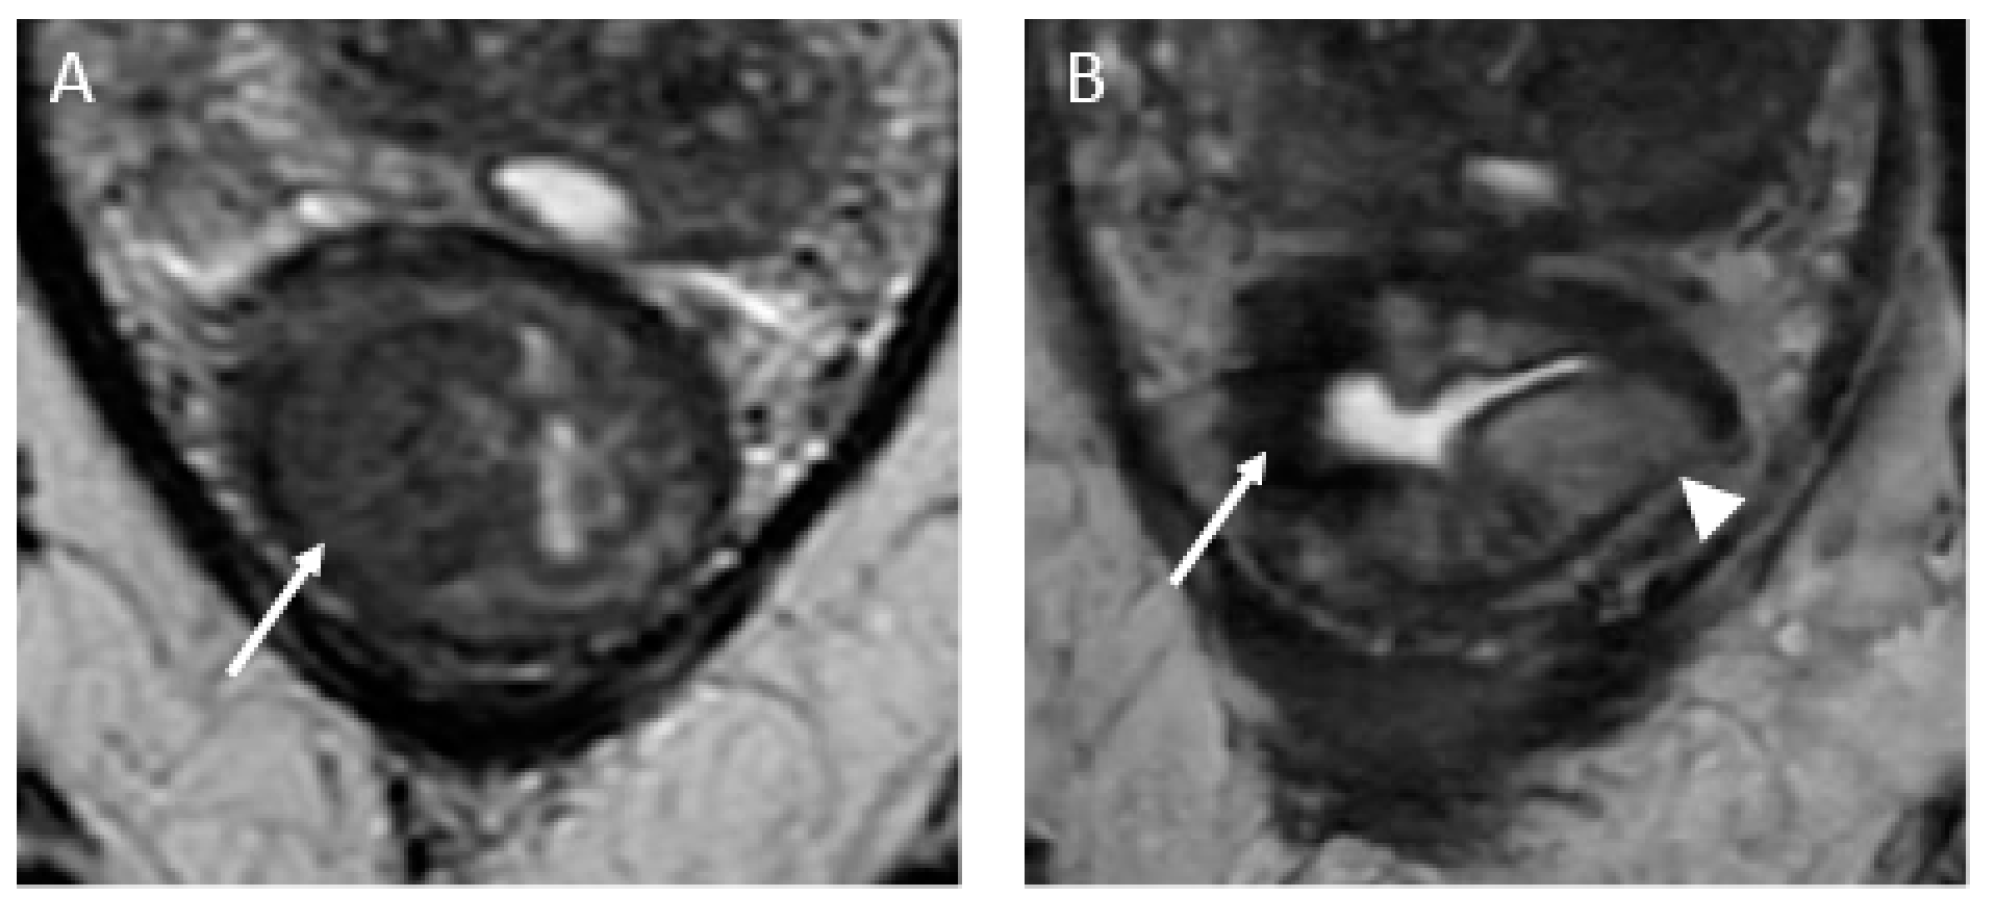

- (c)

- iCR characterizes the scenario where tumor volume experiences a reduction, but discernible residual tumor persists. This response type manifests through persistent diffusion restriction and the persistence of T2 intermediate signal within the tumor bed (Figure 4).